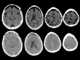

Trauma to brain

A traumatic brain injury (TBI), also known as an intracranial injury, is an injury to the brain caused by an external force. TBI can be classified based on severity (ranging from mild traumatic brain injury [mTBI/concussion] to severe traumatic brain injury), mechanism (closed or penetrating head injury), or other features (e.g., occurring in a specific location or over a widespread area). [Source: Wikipedia ]